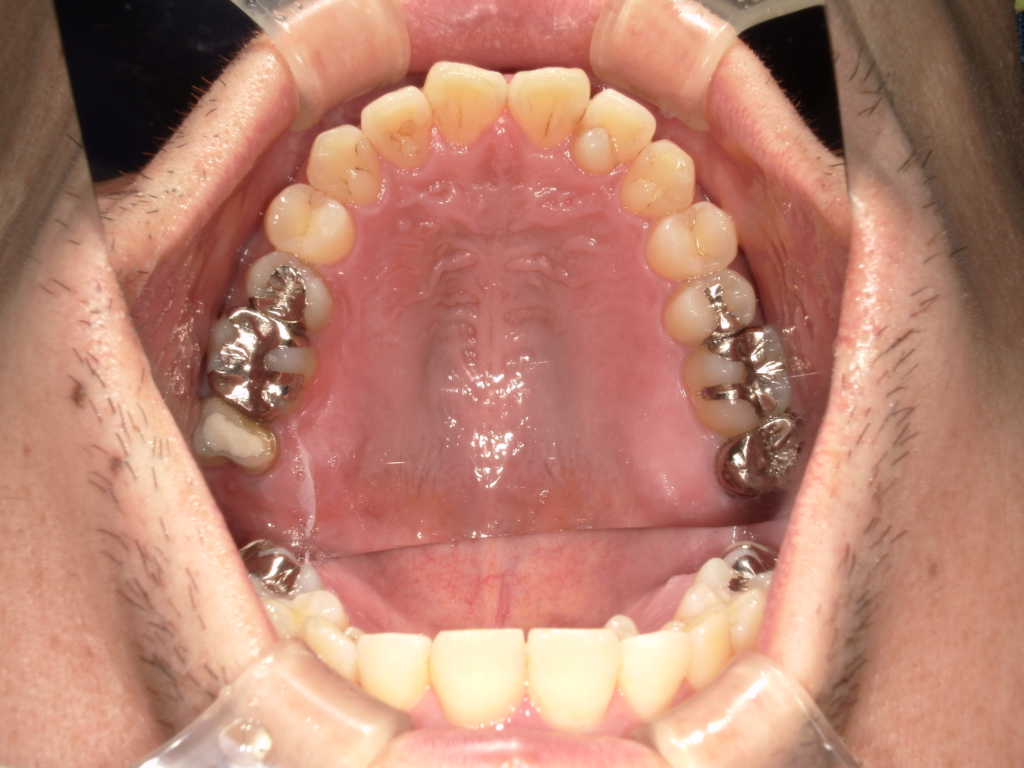

Y様インプラント実例 #44

左の上下の奥歯をインプラントで治療しています。

左下の奥歯は歯を抜くのと同時にインプラントの埋め込みを行っています。

被せものは上下、セラミックスで作っています。

治療前

治療後